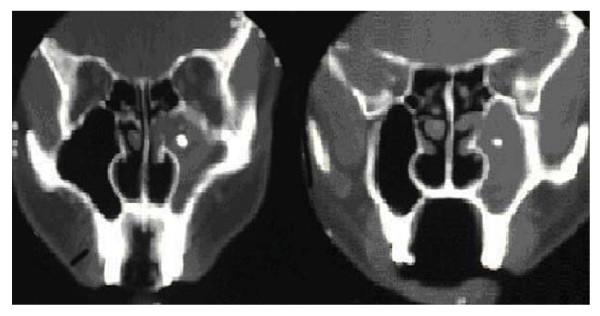

A 45-year-old male presented with a 2-month history of episodic haemoptysis. A pedunculated growth from the inferior nasal turbinate was seen with fibre-optic visualization. Although the patient was empirically started on antibiotic and anti-allergic therapy, there was no improvement after a few weeks and the patient had recurrent episodes of haemoptysis. Fibre-optic visualization was repeated showing bilateral osteomeatal erythema. Computed tomography scan of the paranasal sinuses demonstrated complete opacification of the left maxillary antrum along with a focal area of density comparable to bone. An ectopic, supernumerary molar tooth was found in the left maxillary antrum on endoscopic examination and subsequently removed. In addition, copious purulent discharge was seen. Post-operatively, the patient was treated with a 10-day course of oral amoxicillin-clavulanate. On follow-up, he reported resolution of symptoms.

一名 45 岁男性因 2 个月间歇性咯血就诊。纤维光学检查可见下鼻甲有一带蒂生长物。尽管患者经验性地接受了抗生素和抗过敏治疗,但数周后仍未见改善,且患者反复发作咯血。再次进行纤维光学检查显示双侧中鼻甲红斑。鼻窦计算机断层扫描显示左侧上颌窦完全闭塞,伴有与骨密度相当的局灶性密度区。在内镜检查中发现左侧上颌窦内有一颗异位、额外的磨牙,并随后将其切除。此外,还可见大量脓性分泌物。术后,患者接受了 10 天疗程的口服阿莫西林克拉维酸钾治疗。随访时,患者报告症状已缓解。